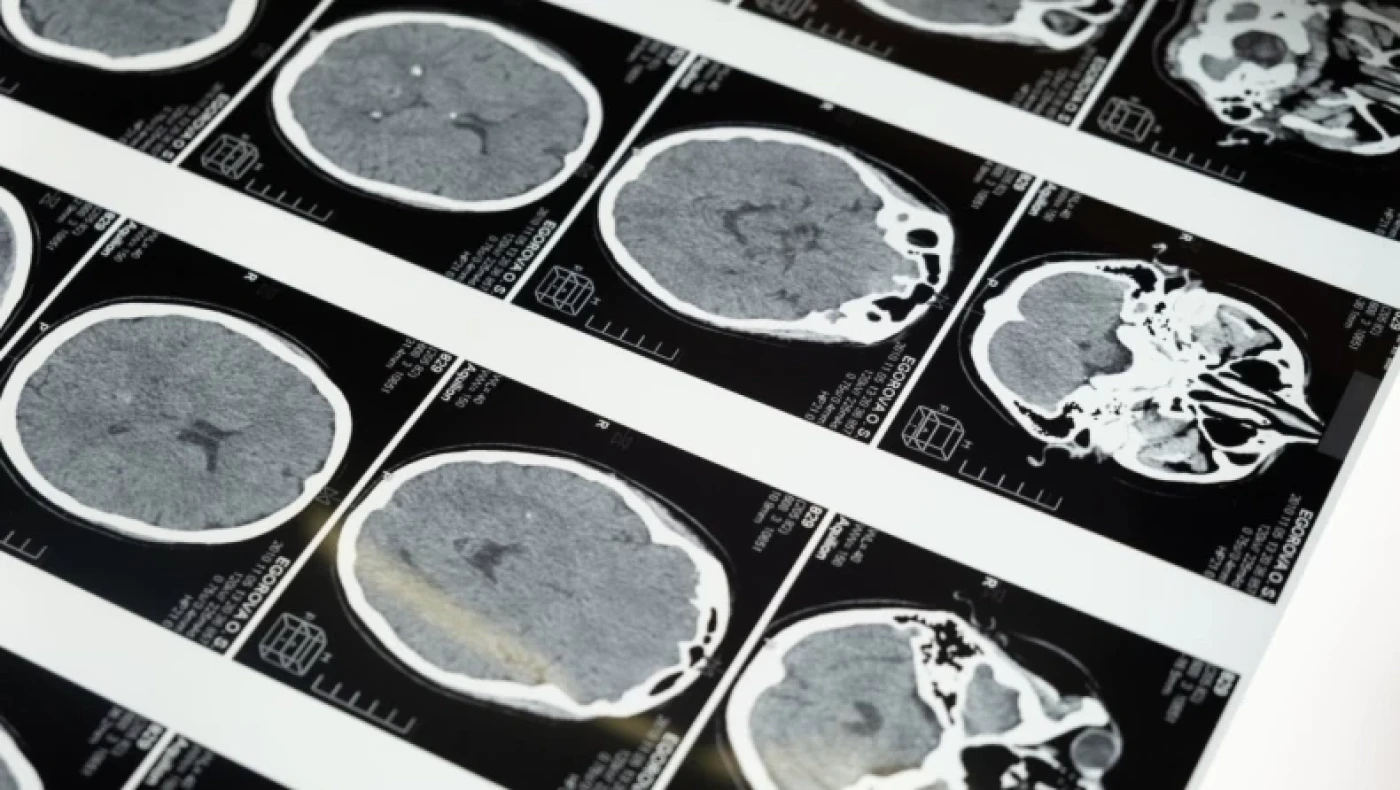

Μια νέα συναρπαστική μελέτη έριξε φως στο πόσο αξιοθαύμαστος είναι ο ανθρώπινος εγκέφαλος. Η έρευνα αφηγείται την ιστορία ενός άνδρα, γνωστού απλώς ως ασθενής Μ, ο οποίος πυροβολήθηκε στο κεφάλι κατά τη διάρκεια του ισπανικού εμφυλίου πολέμου της δεκαετίας του 1930.

Όταν ξεκουραζόταν, χωρίς σημαντικά ερεθίσματα για να επικεντρωθεί, ο 25χρονος έβλεπε τα πράγματα εντελώς ανάποδα, σύμφωνα με την εργασία, η οποία δημοσιεύθηκε στο ισπανικό περιοδικό Journal of Neurology.

Έβλεπε τα πράγματα ανάποδα, ενώ υπέφερε και από άλλες οπτικές επιπλοκές, όπως μια παράξενη κατάσταση κατά την οποία τα χρώματα φαίνονταν ξεκολλημένα από τα αντικείμενά τους και αδυναμία ανίχνευσης της κίνησης.

Έγινε αντικείμενο έντονης γοητείας για τον Ισπανό νευροεπιστήμονα Justo Gonzalo, ο οποίος τον μελέτησε επί 50 χρόνια.Η ανάλυση του Gonzalo οδήγησε τελικά σε μια σημαντική αλλαγή στον τρόπο με τον οποίο κατανοούμε τον εγκέφαλο, κυρίως χάρη στο συμπέρασμά του ότι ο εγκέφαλος δεν είναι απλώς μια συλλογή διακριτών τμημάτων αλλά ένα δυναμικό σύνολο.

Ο ασθενής Μ βοήθησε τον νευρολόγο να δει ότι οι επιπτώσεις της εγκεφαλικής βλάβης εξαρτώνται από το μέγεθος και τη θέση του τραύματος και ότι οι τραυματισμοί δεν καταστρέφουν συγκεκριμένες λειτουργίες, αλλά επηρεάζουν την ισορροπία μιας σειράς λειτουργιών.